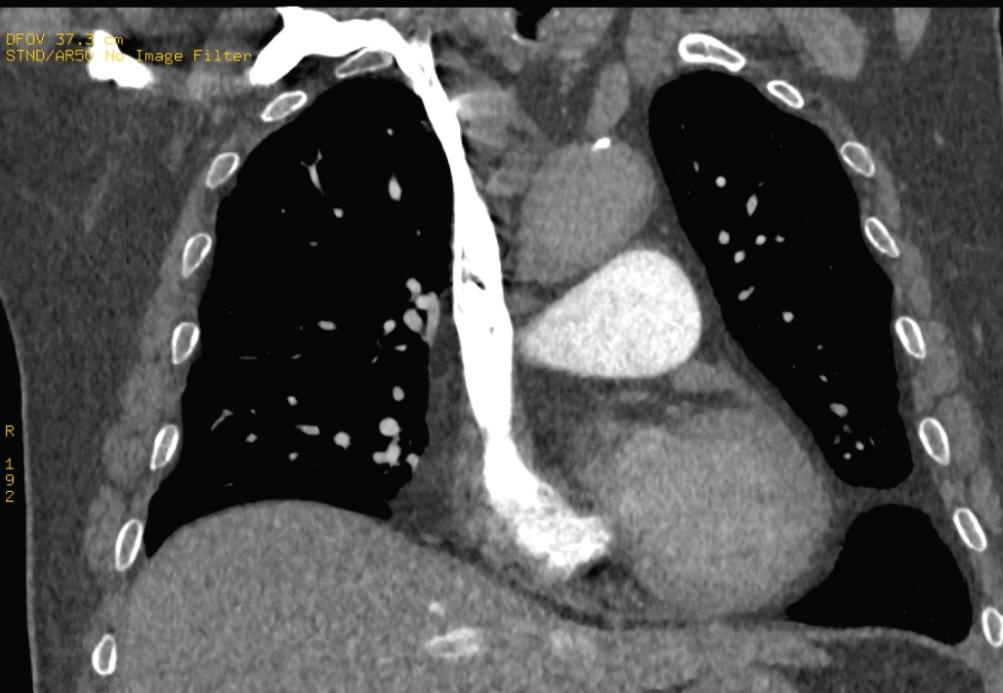

根据此路径可发现当对比剂到达锁骨下静脉、头臂静脉时,左右两侧的路径发生分歧,右锁骨下静脉→右头臂静脉路径距右心房的距离要明显短于左锁骨下静脉→左头臂静脉路径。同时右锁骨下静脉连接右头臂静脉后直接汇入右心房,而左锁骨下静脉连接左头臂静脉的同时需跨越左颈总动脉、头臂干,部分情况下还会受到主动脉弓的影响。

如下图所示

右锁骨下静脉经头臂静脉直接进入上腔静脉